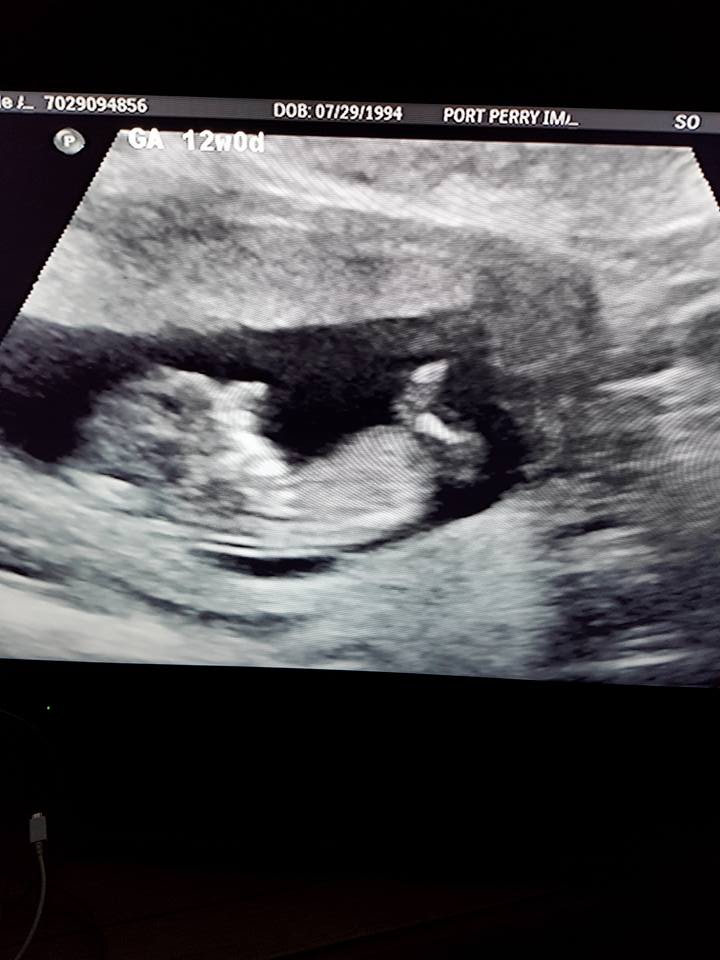

Hi! Just wondering if there is a nub in these photos, and if so, if you would guess it's a boy or girl? 12+0 weeks. Thank you!Attachment 38349Attachment 38350Attachment 38351Attachment 38352Attachment 38353